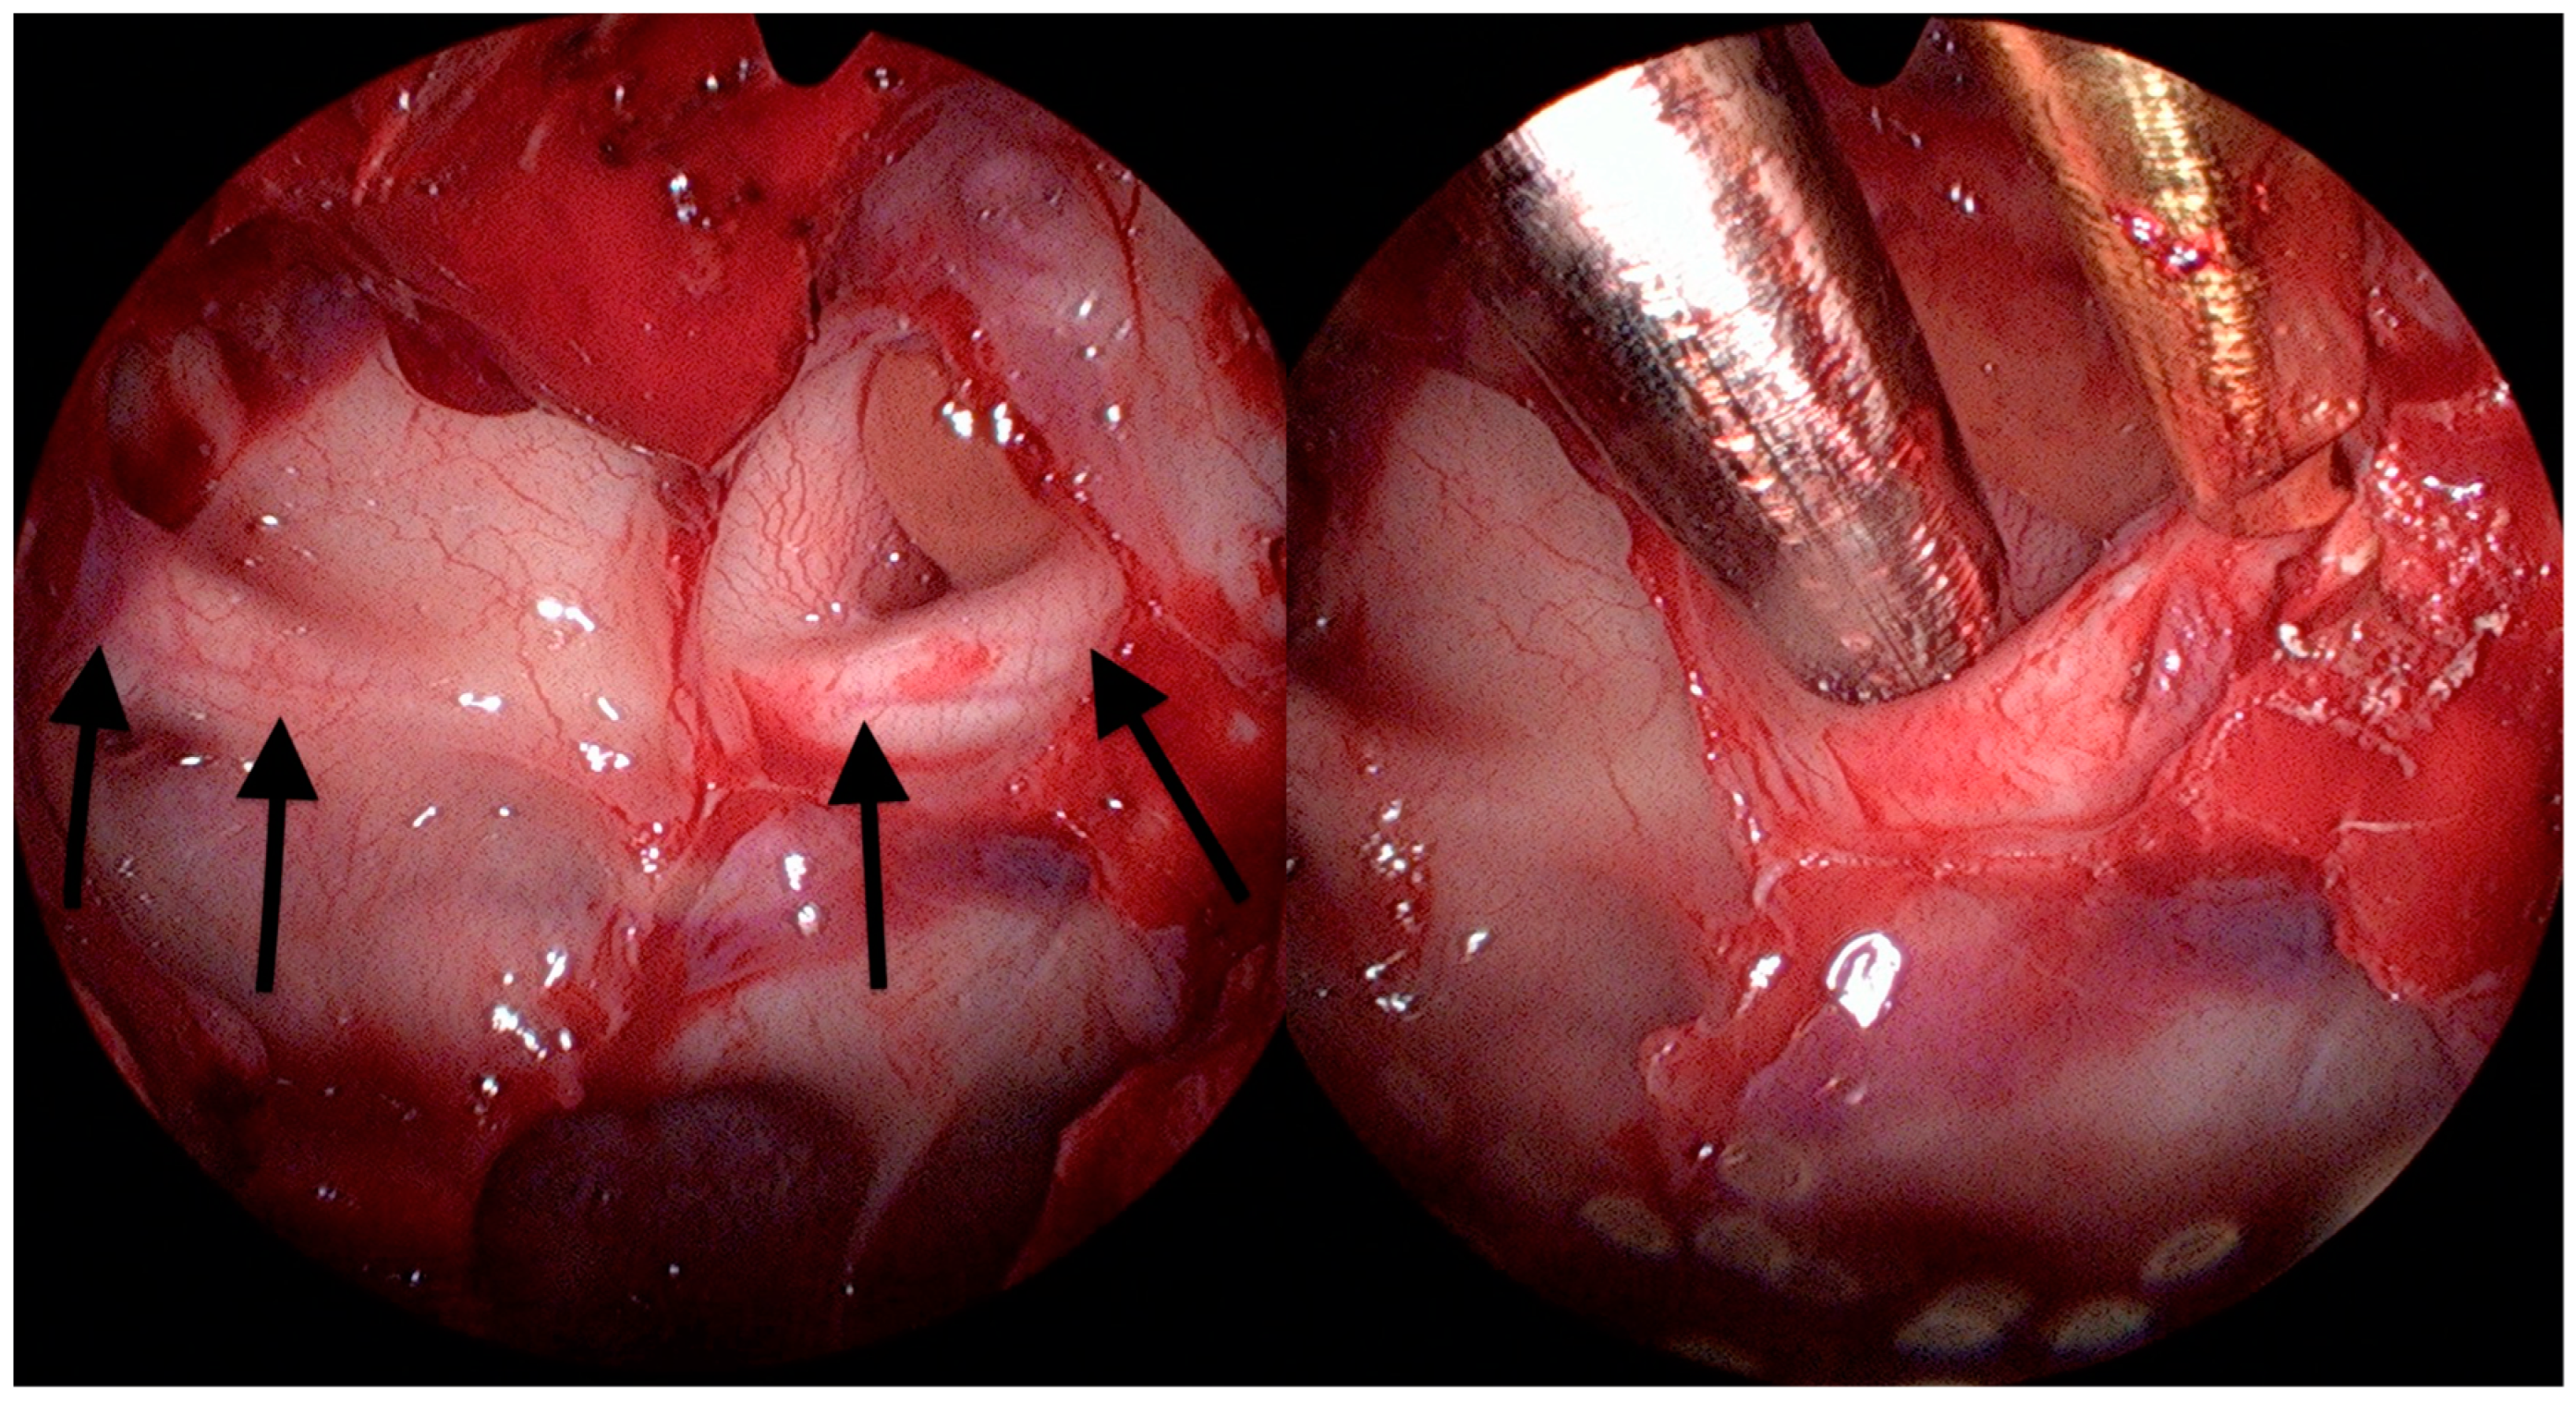

2.3. Surgical Technique

Illustrative Case Report